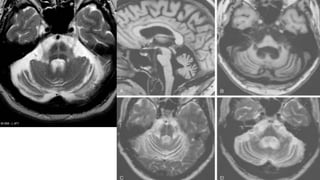

RADIOGRAPHIC FEATURES

•T2 hyperintensities: typically present in the pontocerebellar tracts

• pons: hot cross bun sign (MSA-C)

• middle cerebellar peduncles

• Cerebellum

putaminal findings in MSA-P :

 reduced volume

 reduced GRE and T2 signal relative to globus pallidus

 reduced GRE and T2 signal relative to red nucleus

 abnormal disruption of the normal high T2 linear rim.,

•MSA-C

• disproportionate atrophy of the cerebellum and brainstem (especially olivary nuclei and middle

cerebellar peduncle)